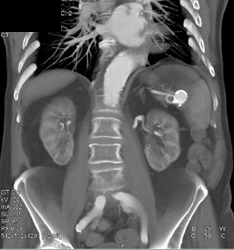

Peripheral Vascular Disease (PVD) With Popliteal Aneurysms